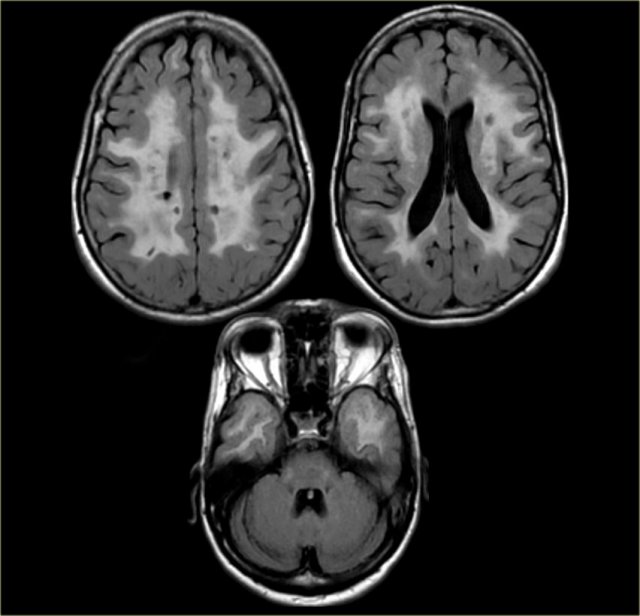

GCA-scale for Global Cortical Atrophy

GCA scale is the mean score for cortical atrophy throughout the complete cerebrum:

• 0: no cortical atrophy

• 1: mild atrophy: opening of sulci

• 2: moderate atrophy: volume loss of gyri

• 3: severe end-stage atrophy: 'knife blade'.

Cortical atrophy is best scored on FLAIR images.

In some neurodegenerative disorders the atrophy is asymmetric and occurs in specific regions.

A radiological report should mention any regional atrophy or asymmetry.